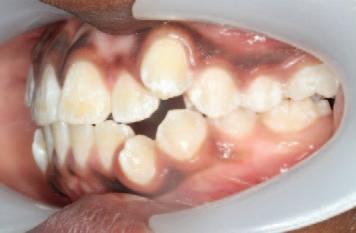

Caries risk assessment in practice

The caries risk status informs the development and implementation of a personalised caries management plan for each patient. Preventive measures, bitewing radiograph intervals and recall planning can be tailored for each patient, in accordance with national and international guidelines.11,13-15 Furthermore, restorative treatment decisions may also be influenced, e.g., interim highviscosity glass ionomer restoration for a high-caries-risk patient with multiple lesions, in contrast to a definitive composite restoration in a patient for whom caries risk can be more readily controlled. Tables 1 and 2 illustrate this tailored approach for different age groups, categorised by caries risk status. These tables represent sample protocols and it is acknowledged that variation will exist depending on local needs, preferred guidance and clinical experience. The personas in Figures 2-4 illustrate the practical application of CRA in general dental practice.

Tim is a 67-year-old farmer who lives two miles from his local village in the countryside. He continues to farm with his adult son and is a keen sports fan. He also enjoys spending time with his family, including three grandchildren living nearby. Tim has enjoyed good heath throughout his life. Last year, his GP prescribed an antihypertensive following a routine medical check-up.

Tim’s oral health has never been a major concern for him. He gives his teeth a quick brush every morning and most evenings with toothpaste. Since starting his medication, he has noticed his mouth feeling dry. He has started to suck hard sweets as he works on the farm. He has also noticed food tending to get stuck between two of his back

Daniel and Kayla have had uneventful visits to their family dentist once a year since infancy. Their teeth are brushed twice daily by their father. It is more challenging for Daniel as he does not always cope well with the flavour of the toothpaste. Recently, Daniel has found it more difficult due to sensitivity. Their dentist advised that Daniel has molar incisor hypomineralisation (MIH) and there was enamel breakdown on his newly erupted lower first permanent molars. Kayla’s teeth appeared normal. Bitewing radiographs showed that Kayla’s teeth were intact, but there were uncavitated lesions evident on Daniel’s primary molars.

teeth, with occasional sensitivity. He attended his dentist for a check-up. His dentist confirmed that his mouth was dry, and radiographs showed that he had two cavities, which required fillings.

FIGURE 3: Persona 2 – Tim.

Persona 2 – Tim